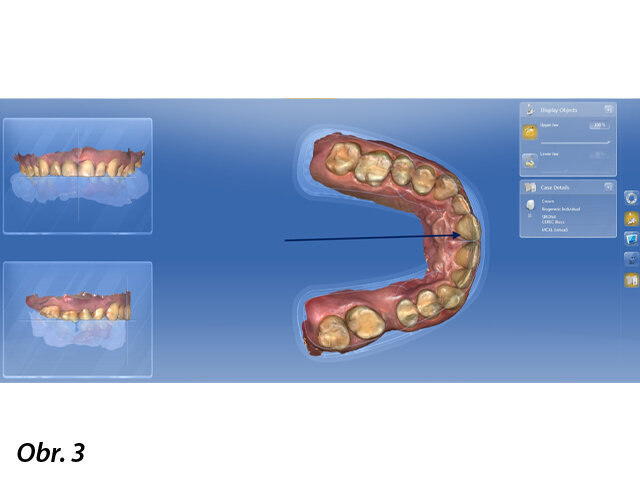

Sken horního zubního oblouku.

Naplánovali jsme jednodobou implantaci s okamžitou tzv. nefunkční korunkovou rekonstrukcí, bez okluzních kontaktů. Zhotovili jsme CBCT vyšetření a dále jsme s pomocí skeneru CEREC Omnicam naskenovali horní i dolní zubní oblouk, a také tzv. buccal scan. Skeny jsme dále odeslali formou souborů STL a se soubory DICOM byly složeny v programu SIMPLANT. V souladu s pravidlem 3A-2B (F. Rojas-Vizcaya) byla naplánována optimální poloha implantátu ANKYLOS C/X B 14, využívající možnosti programu SIMPLANT.

Intraorální sken umožnil zakreslení budoucí protetické rekonstrukce tak, aby bylo možno zhotovit šroubovanou korunku. Bylo to důležité obzvláště ve snaze předejít tzv. cementitis – zánětu vyvolanému cementem.